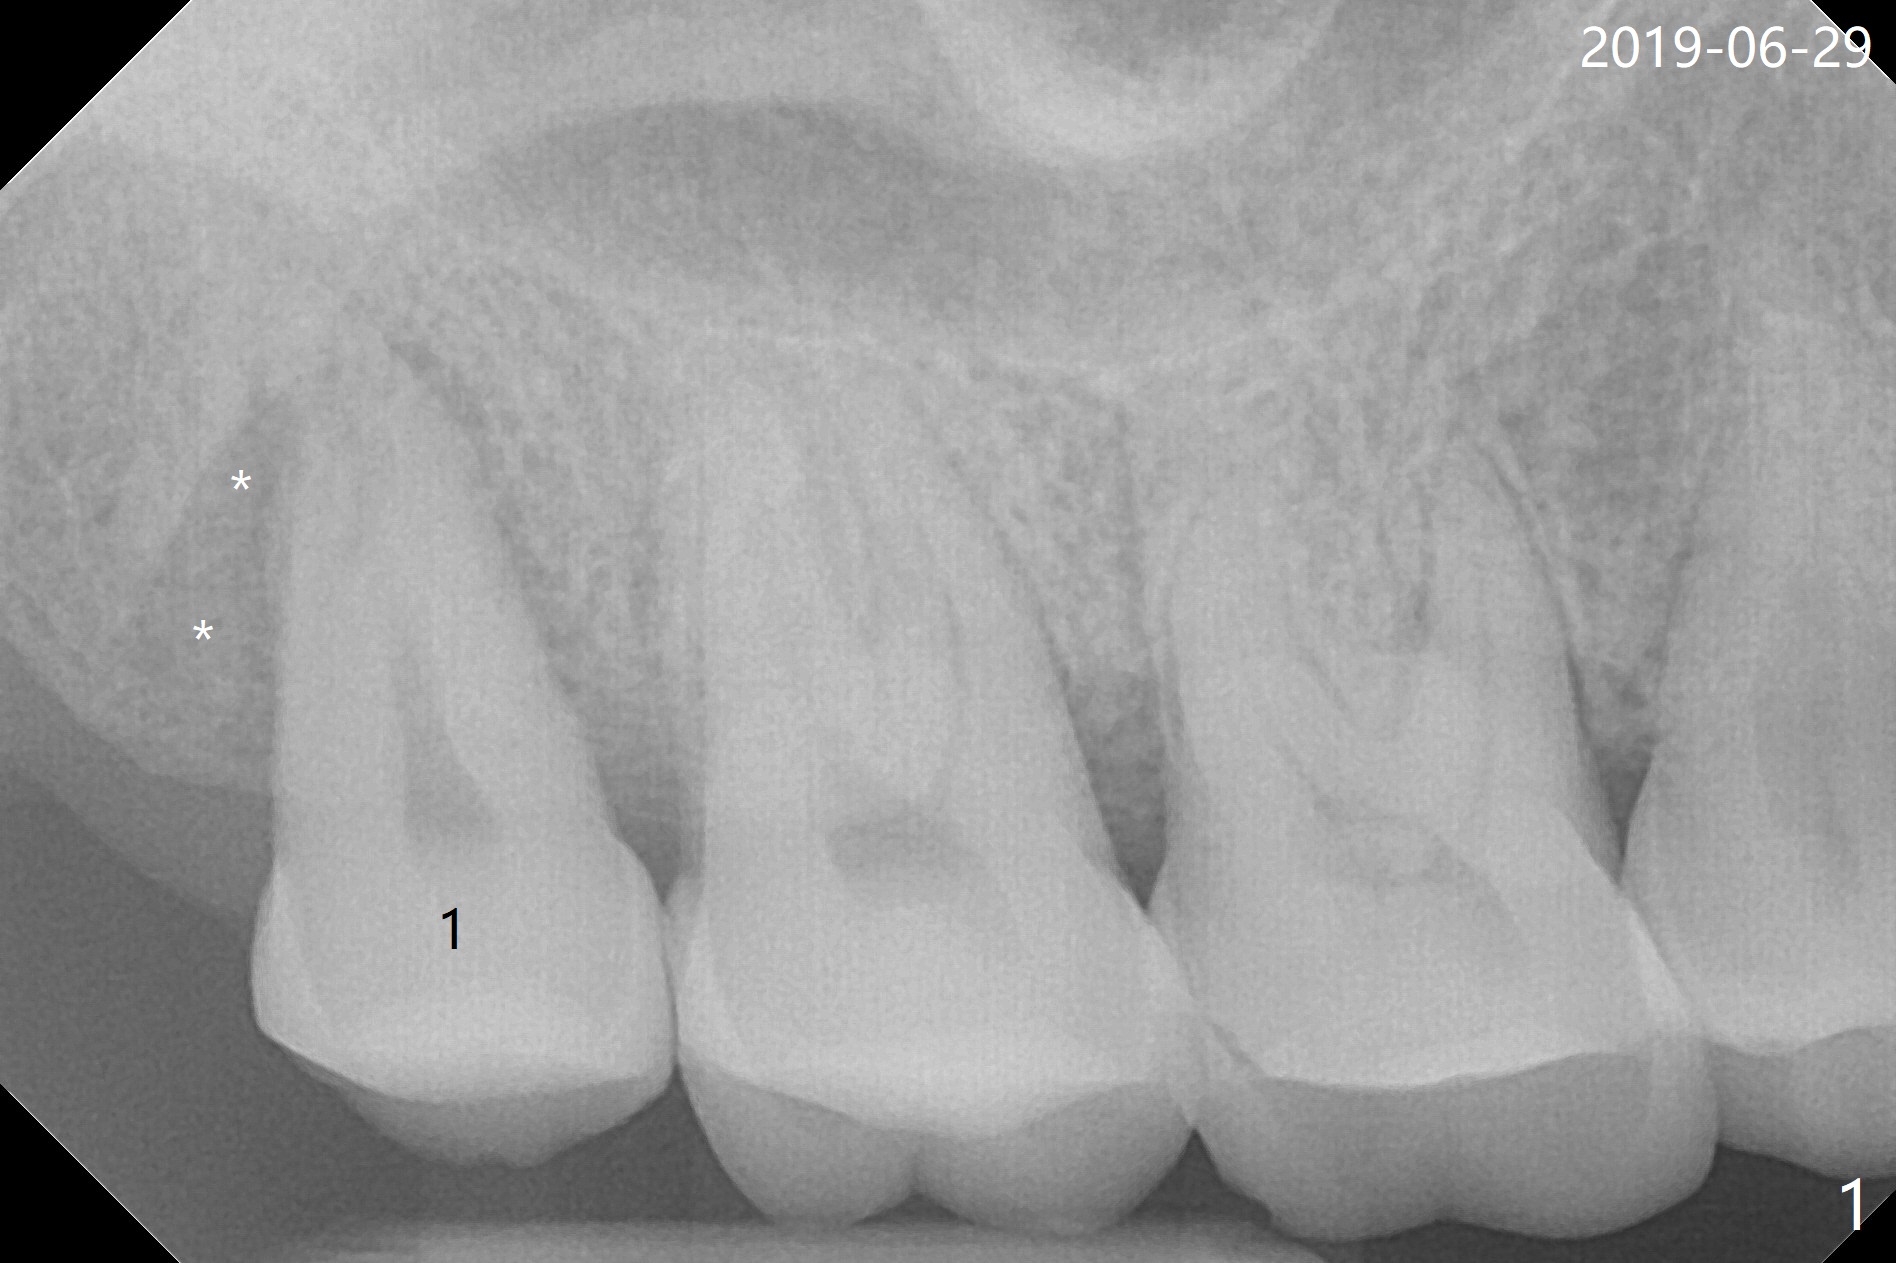

A 56-year-old woman returns to clinic with chief complaint of upper right discomfort (Fig.1) 9 months post #15 implant placement. Clinical exam does not reveal significant finding (periradicular radiolucency (PRRL) at #1 (*) is neglected). Six months later, PRRL at #1 is enlarged (Fig.2 *) with palatal gingival recession, pockets and BOP. The tooth is extracted; its palatal plate is lost, which is consistent with CT taken ~ 1 year earlier (Fig.3). Moreover, the palatal root is incidentally found to be have fractured at #2 (Fig.3,5 *), in the same manner as the tooth #15. Bone loss and root fracture are related to bruxism. Since the tooth #32 is present, an immediate implant could have been placed at #1 (Fig.4).